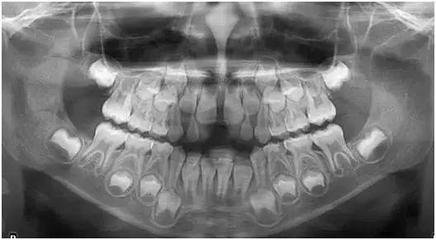

深圳牙齒矯正醫院醫生解釋,你所謂的牙列全景圖X光,其實名字叫做全景片,也叫曲麵斷層片,是可以看到口腔內(nei) 所有的牙齒情況,包括有無智齒、智齒位置和方向如何、有無牙齒缺失、有無蛀牙、有無不良修複體(ti) 、牙槽骨條件好不好等等,所以到醫院後怎麽(me) 掛號以及怎麽(me) 準確告知醫生很關(guan) 鍵。

這種全景片的拍片價(jia) 格一般很便宜,大致在百多元到兩(liang) 百元左右,基本上是少買(mai) 幾包煙,少買(mai) 幾個(ge) 零食,以及少買(mai) 一隻口紅就能支付的,所以大家不用擔心這個(ge) 價(jia) 格。可以放心到專(zhuan) 業(ye) 的口腔醫院進行,注意一定是專(zhuan) 業(ye) 正規機構,而不是隨便找一家診所進行,當然需要出片子的話,更需要注意選擇醫院,因為(wei) 部分醫院即便是綜合口腔科,也是不出片子的。